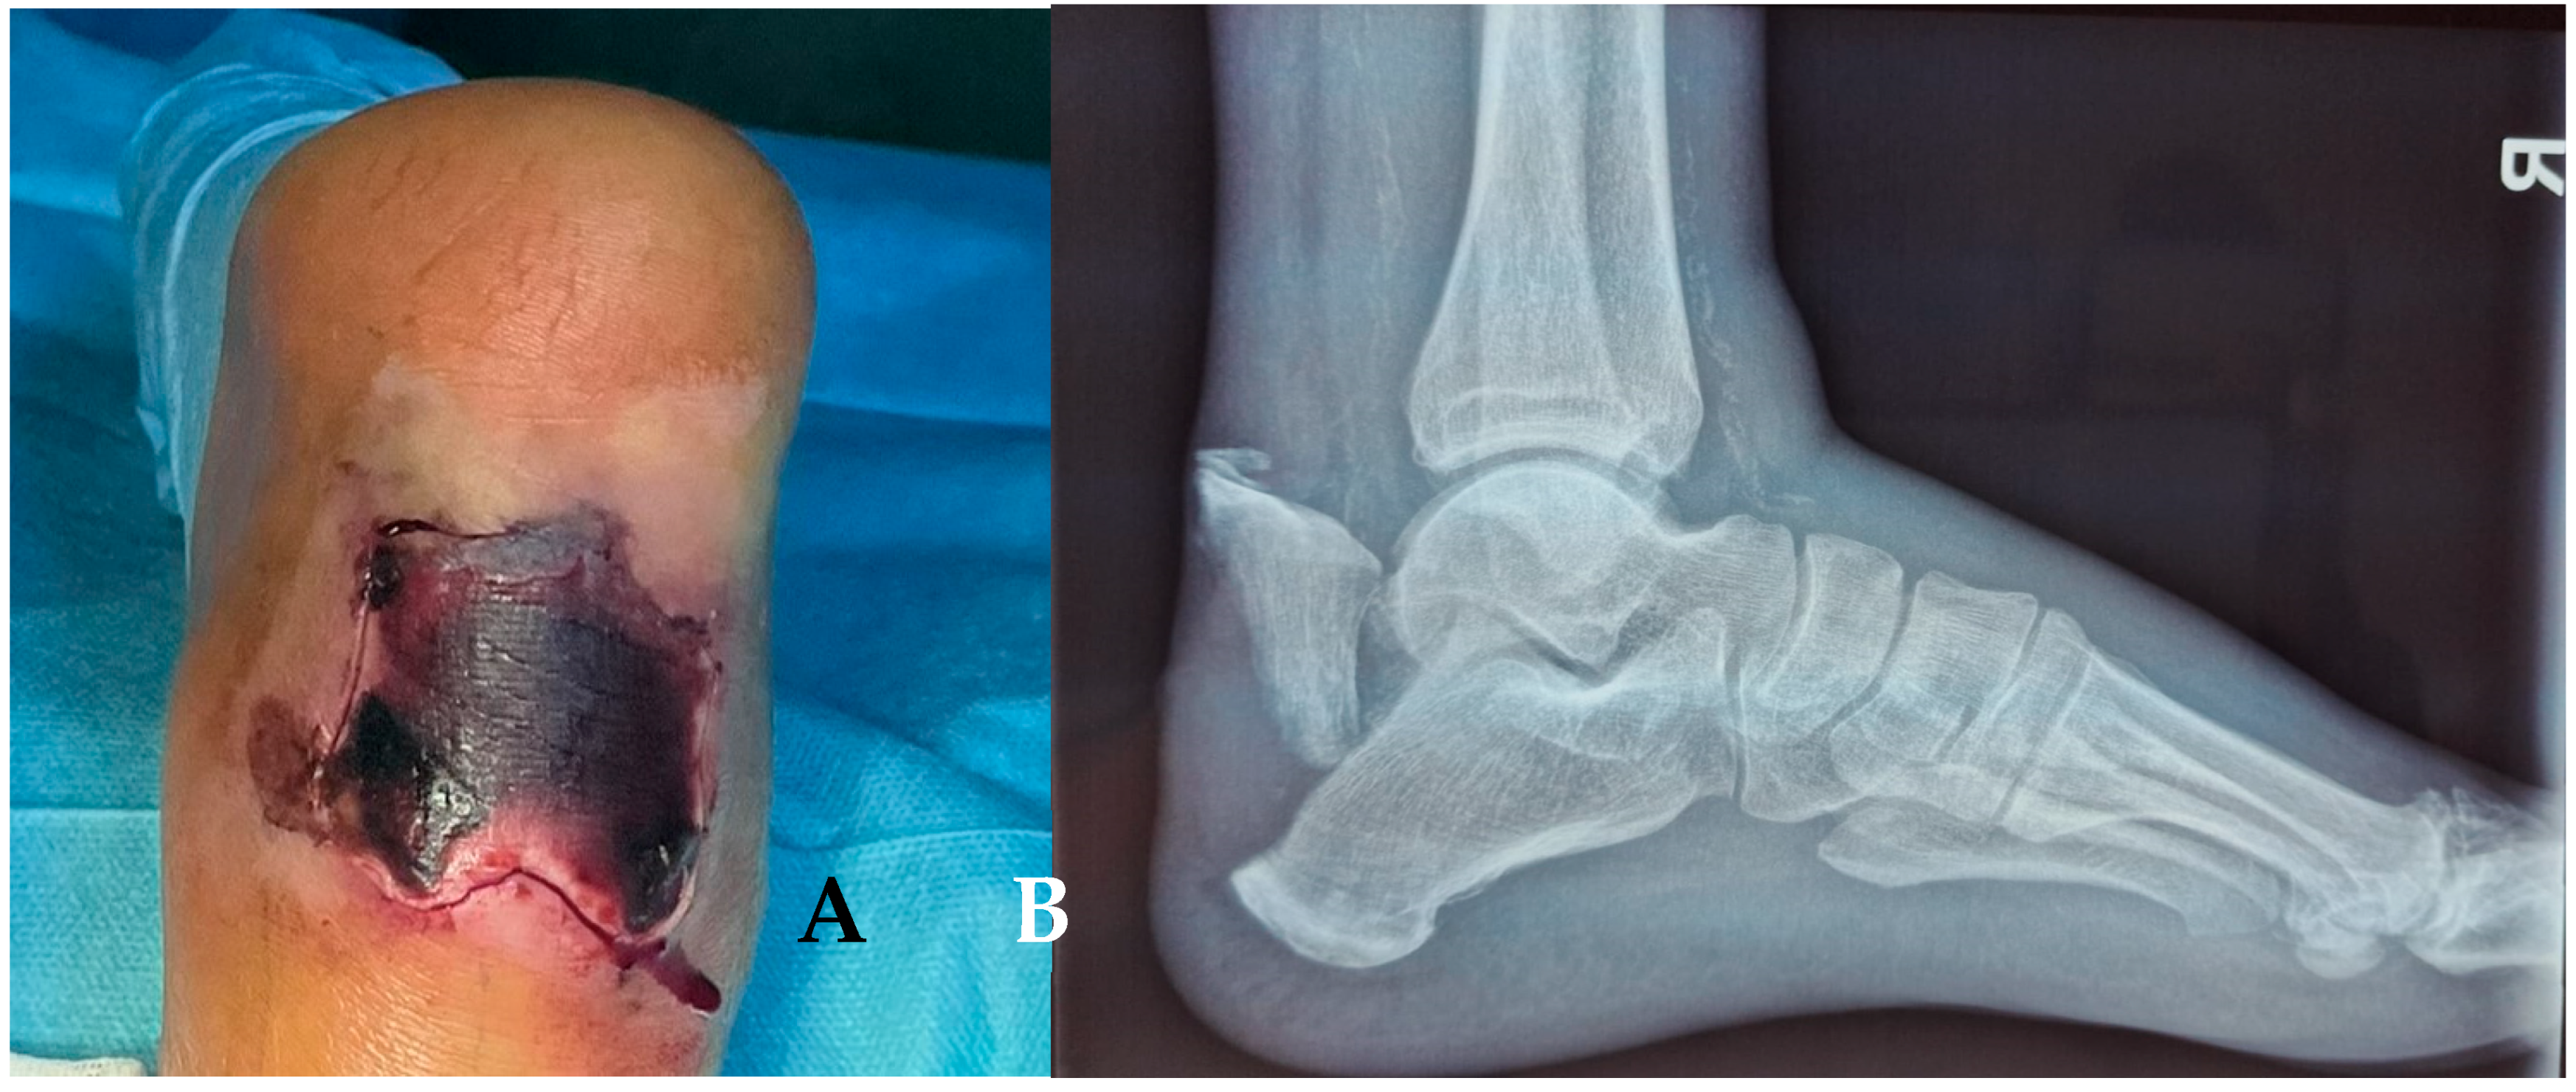

Figure 8. (A) Necrosis of the soft tissue covering the fracture site, 3 weeks after fracture. (B) X-ray of the ankle.

A 72-year-old male patient presents in the emergency room complaining of pain at the level of the right calcaneus, which started 3 weeks before when the patient sustained a fall from a ladder. The mechanism of the trauma was a combination of contusion at the level of the insertion of the Achilles Tendon and traction mixed with dorsiflexion of the foot. The pain was neglected, but at the level of the injury, the skin color started to change. The patient presented with an area of 5 cm × 5 cm of necrosis, acute pain in the dorsal aspect of the calcaneus, and the impossibility of full weight bearing and walking. The X-ray shows a calcaneal fracture (Müller/AO/OTA classification: 82-A1). Figure 8. The soft tissue area covering the calcaneal tuberosity presented this alteration of vascularization because of the fracture fragment attached to the Achilles tendon, which was pulled backwards and upward, generating pressure on the soft tissue from the inside.